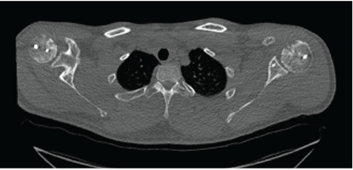

Figure 3: Postoperative Computed tomography (CT) illustrating proper incorporation of the humeral head using osteochondral allograft transplantation.

Postoperative computed tomography at 3 months indicated the subchondral portion of the graft in near-anatomic alignment with signs of bone bridging and healing, concluding proper incorporation of the graft to the surrounding bone. All shoulders were free from re-dislocation at time of final follow-up with no signs of degenerative changes or avascular necrosis on computed tomography (mean follow-up 6 months).